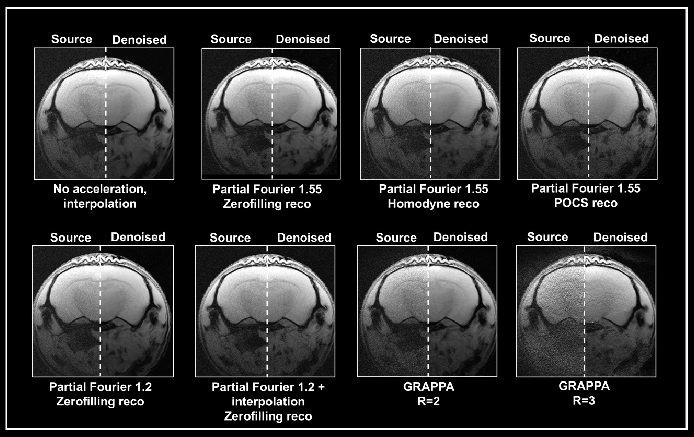

Multiple methods to accelerate MRI acquisitions by employing temporal or spatiotemporal redundancy of the images have been used in the literature.6 Approaches such as parallel imaging deliver structured noise in the reconstructed image as the decreased data sampling and noise amplification result from the parallel reconstruction algorithm.1

Ex vivo brain data were obtained with either partial Fourier or the multi-coil generalized auto-calibrating partial parallel acquisition (GRAPPA) approach (Fig. 5). Data obtained without acceleration served as a reference. Acceleration translated into an up to 3-fold decrease in acquisition times compared to the protocol when no averaging was used.

Figure 5. Denoising of accelerated brain data. Ex vivo T1-weighted FLASH data of a fixed mouse head were acquired at 9.4 Tesla. Data were either acquired with no acceleration, with partial Fourier (in Read), partial Fourier and interpolation (1.35 in Read and Phase), or with multi-coil parallel imaging technique GRAPPA. For GRAPPA, an acceleration factor (R) of 2 and 3 was chosen, respectively. Partial Fourier images were reconstructed either with zerofilling, homodyne, or POCS, as indicated. All images are shown with no denoising (Source) and after denoising (Denoised) with a Strong network, applying a pre-denoising level of 50% and denoising level of 70%. Image Credit: Bruker BioSpin Group

A denoising level of 70% led to more residual noise in data obtained with a partial Fourier 1.55 compared to data obtained without acceleration. The effect was most significant in homodyne-reconstructed data and lower in zero-filled data. Furthermore, denoising of these accelerated datasets led to image blurring, which was also most robust in homodyne-reconstructed images and lowest in images that were reconstructed with zero-filling.

Obtaining images with partial Fourier 1.2 led to less residual noise and normal image appearance when denoised with 70%. Denoising was ineffective, however, when combining a partial Fourier with interpolation (1.35 in Read and Phase) with the source and the denoised image having similar appearance.

Grappa acceleration led to noisier images than in acquisition with partial Fourier. Reconstructing the obtained data with the denoising algorithm removed noise from the GRAPPA image obtained with an acceleration factor 2.

However, the noise is not fully removed in the image obtained with an acceleration factor 3. Furthermore, reconstruction artifacts and loss of tissue contrast unrelated to the denoising reconstruction are visible.

This demonstrates that the algorithm may be unable to work with data that has a noise characteristic different from the noise that the networks have been trained with (i.e., without acceleration and interpolation). Yet, the outcome is dependent on the selected acquisition and reconstruction parameters.